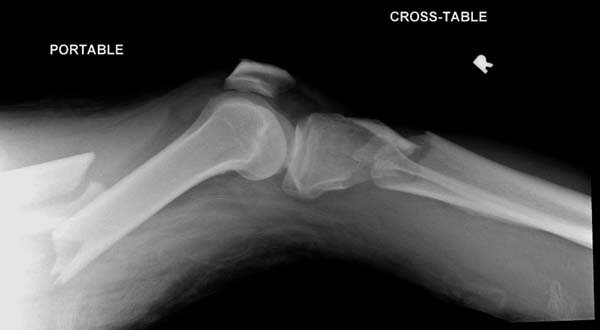

Здесь, кроме перелома верхней трети голени, имеется вовлечение сустава, и, чтобы не пропустить смещение суставной поверхности, надо делать КТ. Срезы КТ покажут о необходимости субхондральной фиксации, которая проводится 3.5 мм параллельными шурупами (Raft technique). Не имеет значения, как проводить: отдельно субхондрально или через верхний ряд пластины. Главная задача фиксации удержать суставную поверхность от коллапса в вальгус или варус.

Здесь случай, так называемого floating knee перелома выше и ниже коленного сустава.

Имя     : 3 Proximal tibia injury knee.JPG